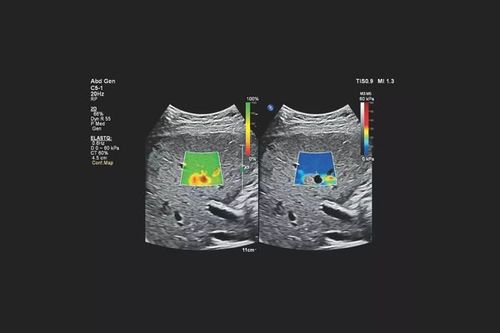

A rheumatic nodule can be visualized using both conventional (gray-scale) and elastography ultrasound. On a standard ultrasound image, the area appears relatively homogeneous, without clearly defined soft or fluid regions. However, when elastography is applied, softer areas (green, yellow, red) can be visualized, while the surrounding tissues appear stiffer (blue)